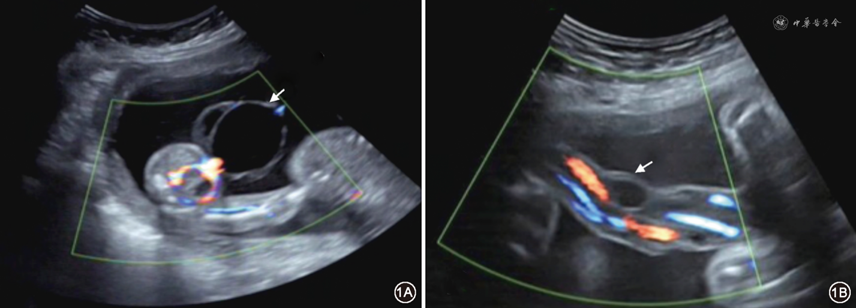

脐带囊肿诊断标准[11]:脐带内部或附着于脐带的无回声肿块,包膜完整,彩色多普勒示囊肿内部无血流信号(图1)。记录囊肿的位置、数量、大小和形态等特点。